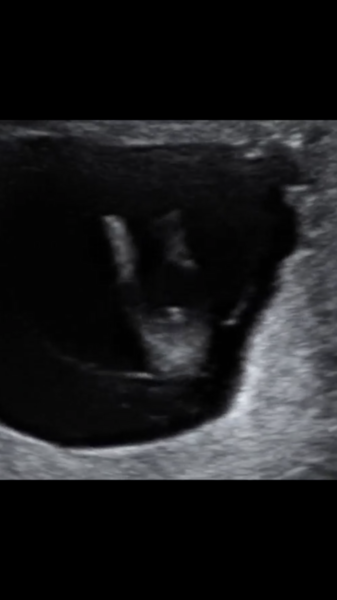

Nifty bloods and scan done. Consultant was able to tell us the sex (said over 90% certain) but nifty bloods will confirm in less than 9 days. Will attach a pic for you to see. That’s not the cord...

Congrats @Whichoneisit That's so cool! What a clear picture!

I guess the cord comment means it's a boy which?

Nice pic which I’ve been considering the NIPT test privately but I think I’ll wait to see what the Combined comes back with first. My SIL in North America gets the Harmony test as standard with her mat care, so they’ve always known the sex very early on.